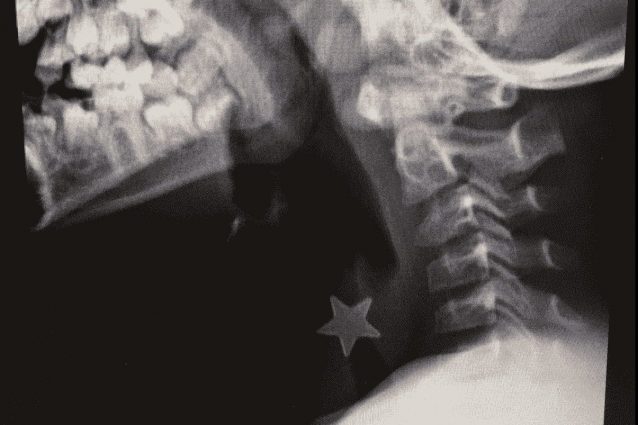

Un bambino di otto anni è stato salvato dai medici dell'ospedale Niguarda di Milano dopo aver inalato inavvertitamente un pezzo di metallo, a forma di stellina, con diametro di oltre un centimetro che gli si era bloccato nella trachea. Ogni anno al nosocomio milanese arrivano circa 15 bambini con problemi simili.